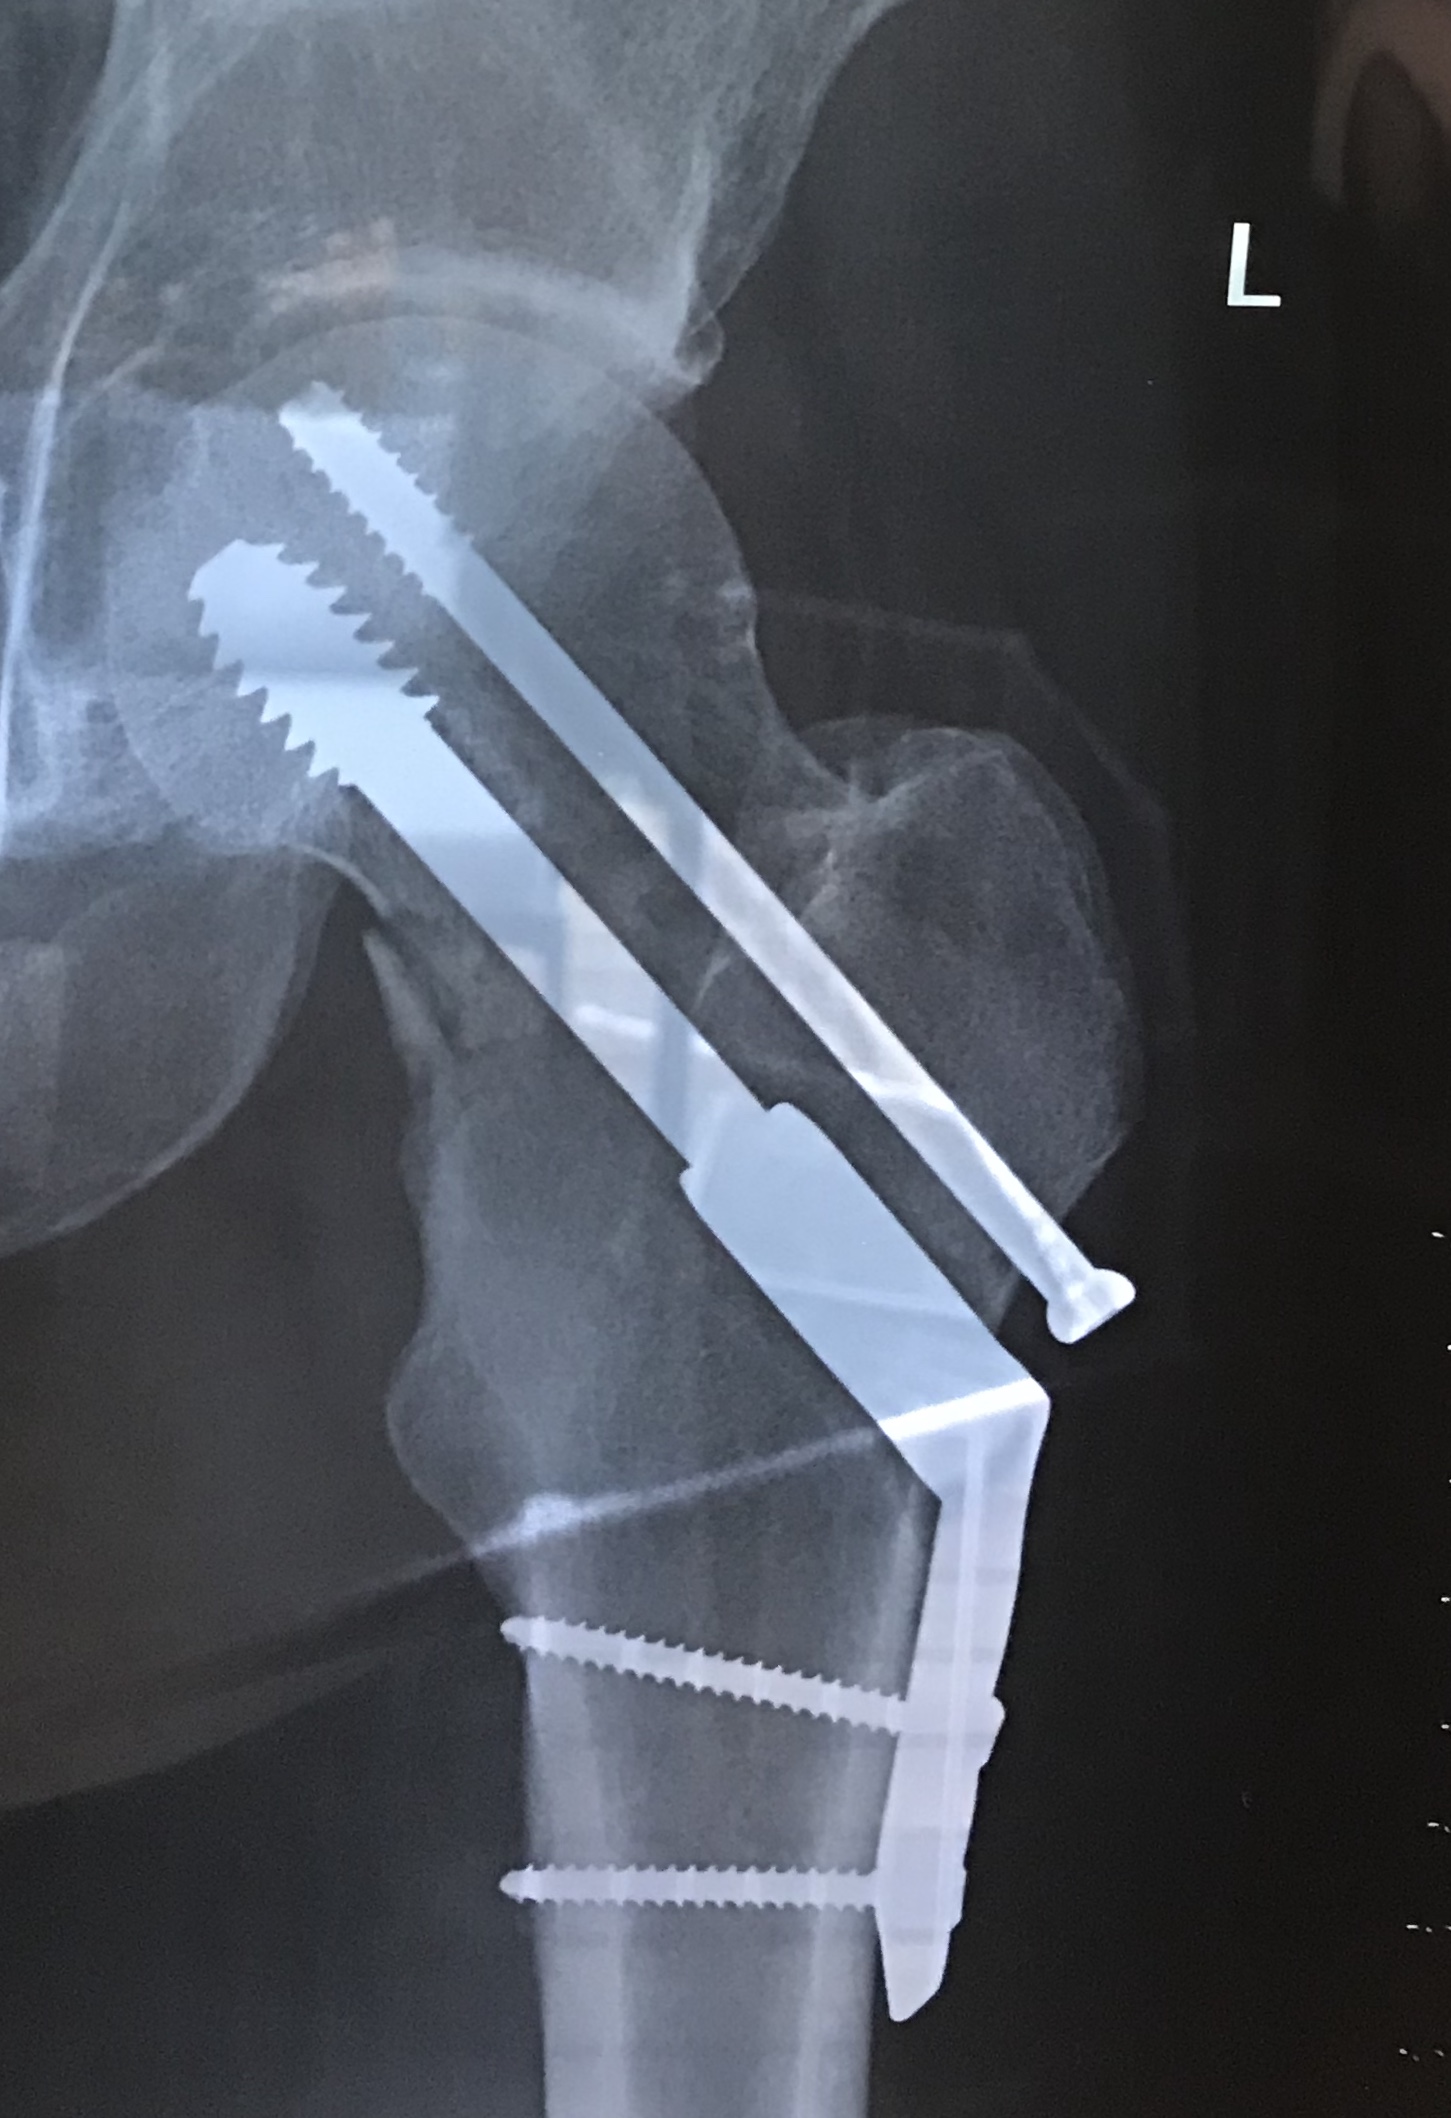

I was hit by an SUV on March 24, 2018, towards the end of a 6.5 hour training ride with a friend. The crash resulted in several injuries including a badly broken left hip. I was operated on several hours later and put back together admirably by a great surgeon with some impressive titanium bolts, rod & screws! (Thank God for modern western medicine, I say.) The surgeons told me that I was to be 50% weight bearing on the injured leg immediately, so the very next morning they turned up at my hospital bed with a walking frame and insisted I get up. Quite amazing really, and so rehab started within 24 hours of the accident.